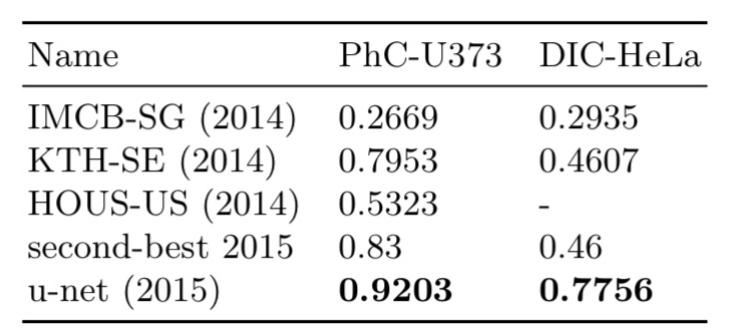

下面是U-Net在两种不同的分割任务中的应用效果

1、U-Net应用于光学显微图像中的细胞分割任务

ISBI细胞跟踪挑战的结果。(a)“PhC-U373”数据集的输入图像的一部分 (b)分割结果(青色掩模)和人工标注的GT(黄色边框) (c)“DIC-HeLa”数据集的输入图像 (d)分割结果(随机彩色掩模)和人工GT(黄色边框)

评估结果:包含35个部分注释的训练图像。实现了92%的平均IOU

其中“DIC-HeLa”另外一个数据集,这里不做介绍了。